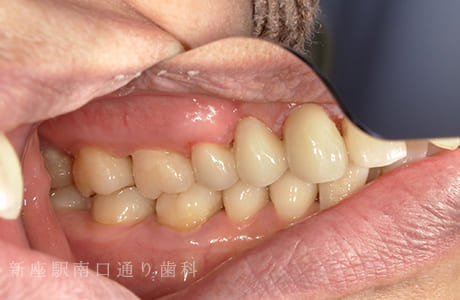

CASE.04

右上にフルジルコニアブリッジで

修復した症例

術前

術中

術後年

- 主訴

- 歯がないところを治したい

- 治療法

- 右上にフルジルコニアブリッジで修復

- 治療期間

- 1ヶ月半

- 費用

- ¥280,000(税込)

【リスク・副作用】

過度の咬合や衝撃で割れることがあります。治療直後は歯や歯茎に一時的な違和感や痛みが出ることがあります。